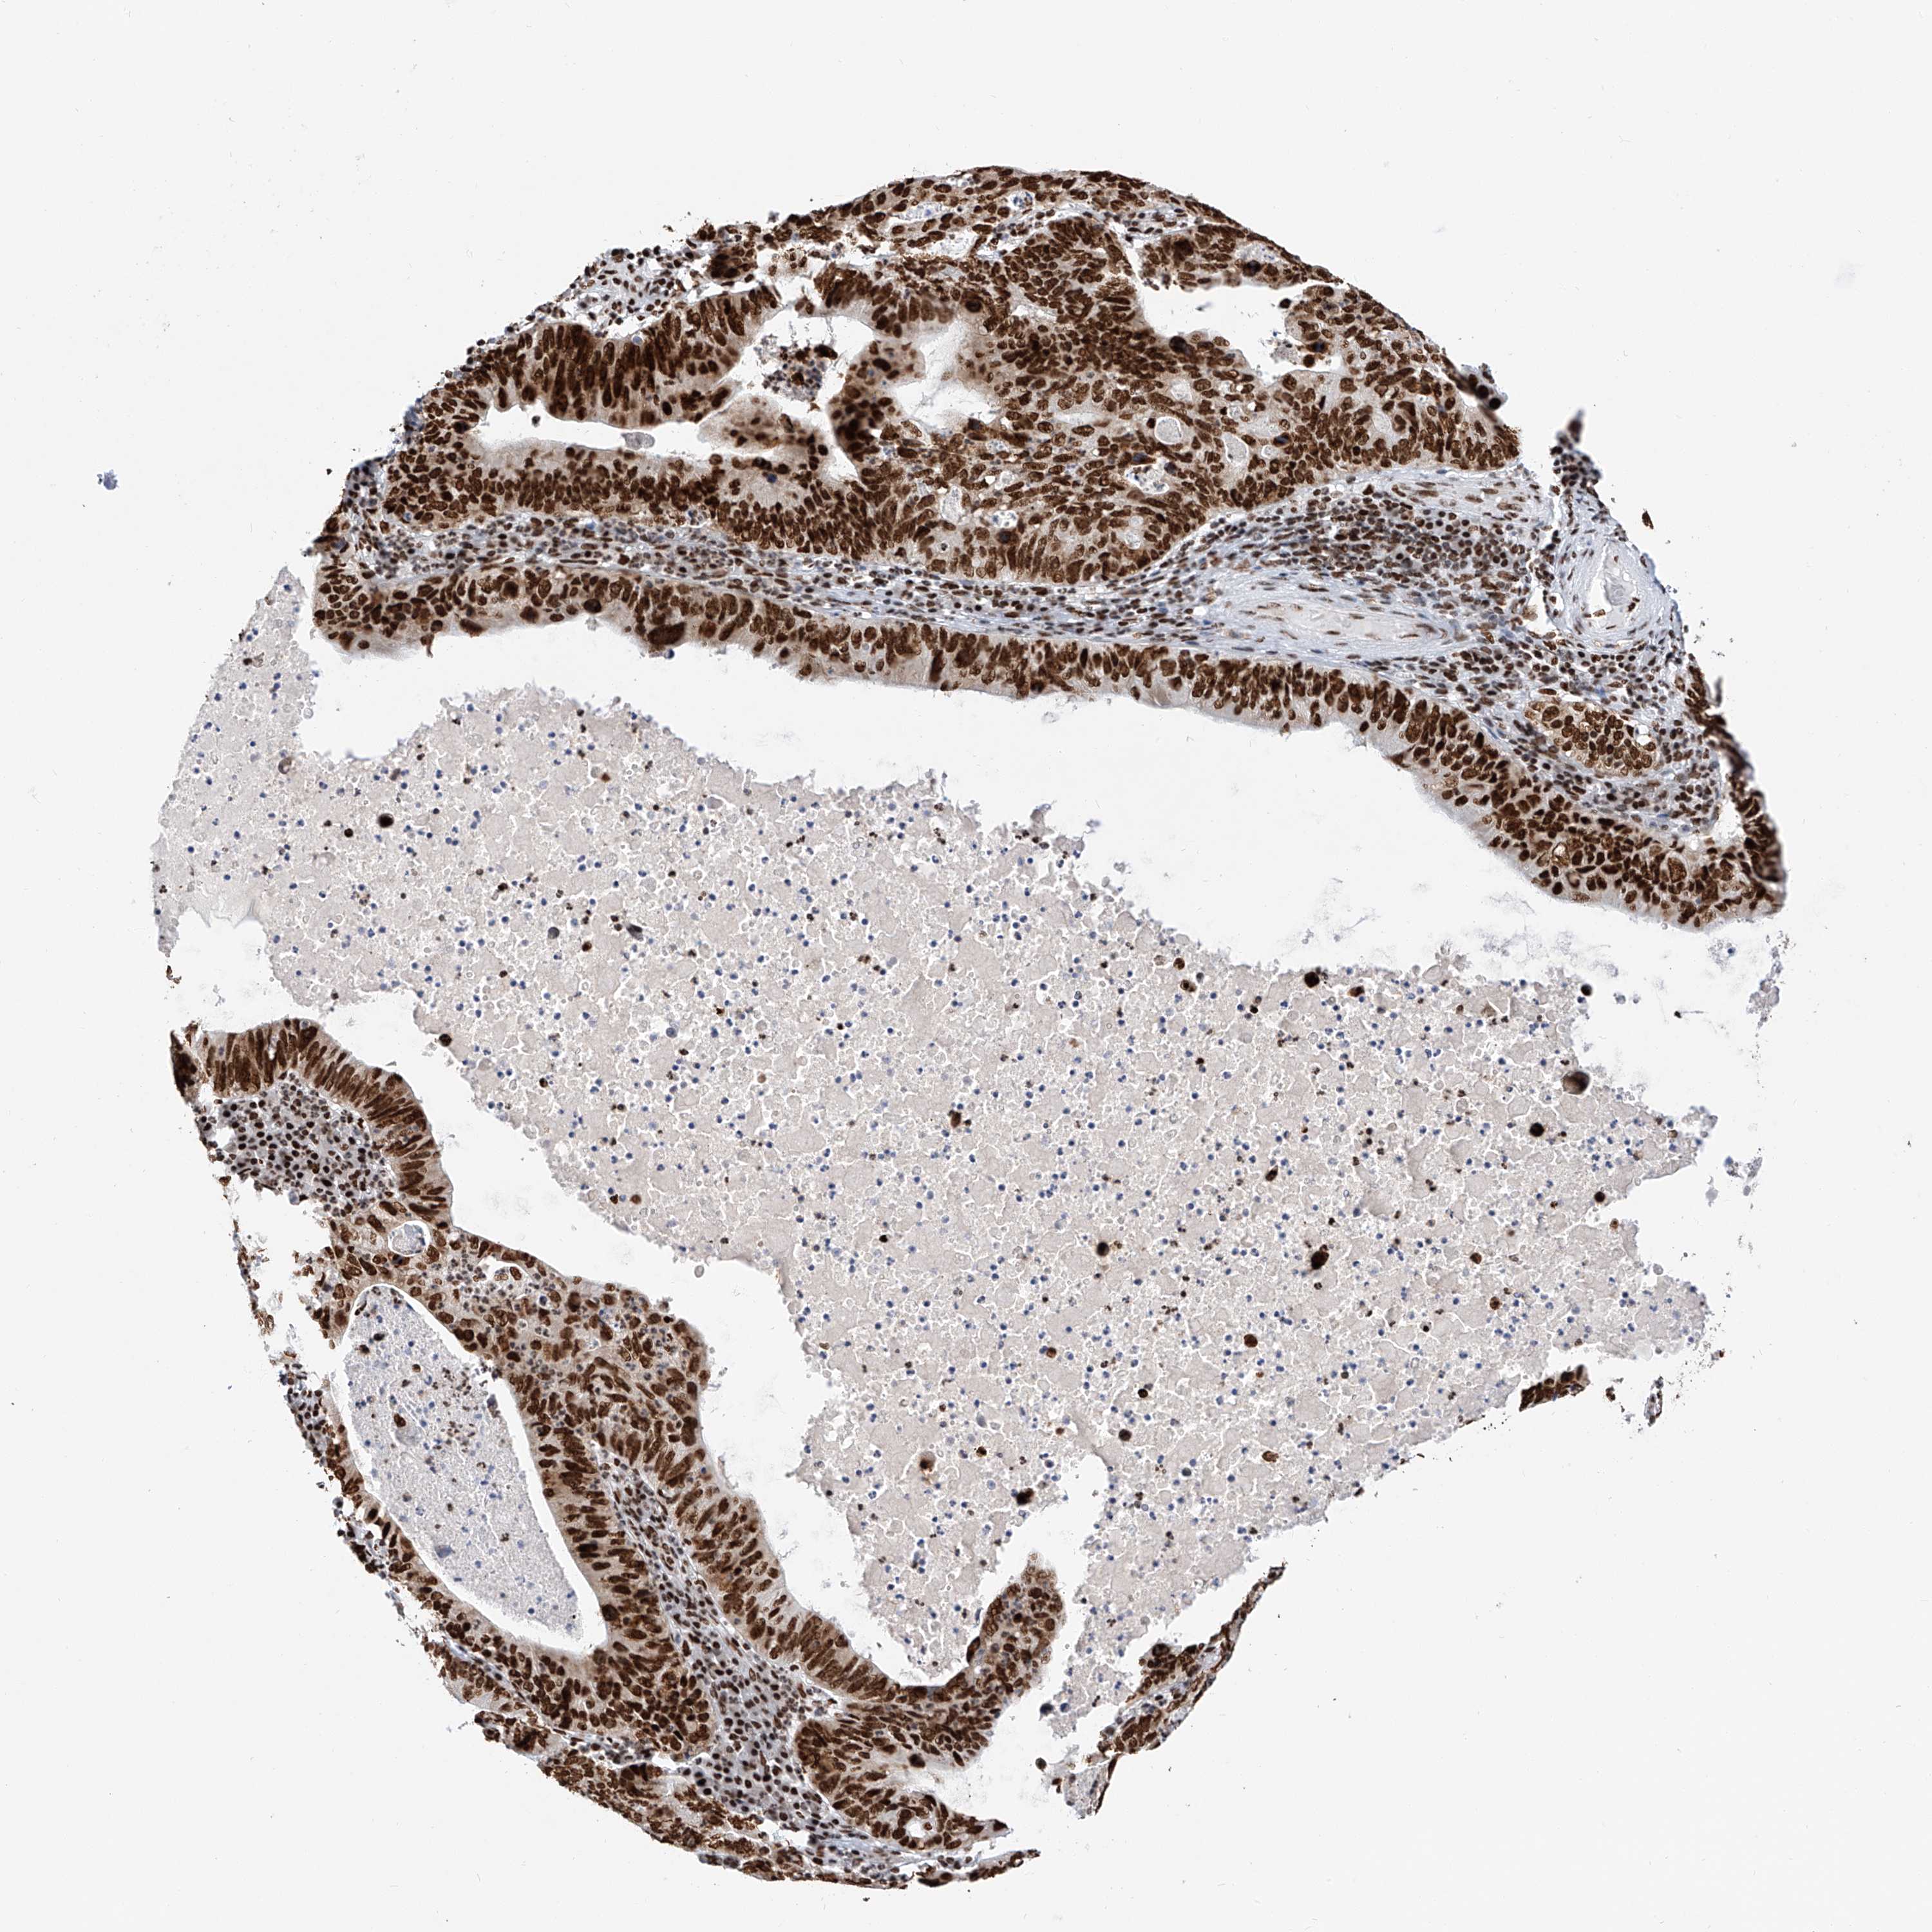

STOMACH CANCER - Protein expressioni

A mouse-over function shows sample information and annotation data. Click on an image to view it in a full screen mode. Samples can be filtered based on level of antibody staining by selecting one or several of the following categories: high, medium, low and not detected. The assay and annotation is described here.

Note that samples used for immunohistochemistry by the Human Protein Atlas do not correspond to samples in the TCGA dataset.

Antibody stainingi

Antibody staining in the annotated cell types in the current human tissue is reported as not detected, low, medium, or high, based on conventional immunohistochemistry profiling in selected tissues. This score is based on the combination of the staining intensity and fraction of stained cells.

Each image is clickable and will lead to virtual microscopy that enables deeper exploration of all samples and also displays staining intensity scores, fraction scores and subcellular localization as well as patient and tissue information for each sample.

Antibody HPA029005

Antibody CAB034889

Staining

High

Medium

Low

Not detected

Intensity

Strong

Moderate

Weak

Negative

Quantity

>75%

75%-25%

<25%

None

Location

Nuclear

Cytoplasmic/membranous

Cytoplasmic/membranous,nuclear

Adenocarcinoma, NOS